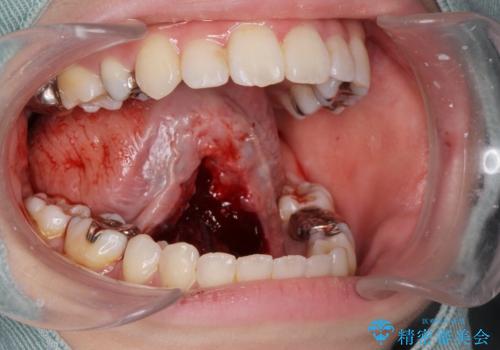

- 舌が動かしにくく、過去に舌小帯切除を行ったがあまり切除されず後戻りをしたため、舌小帯切除を希望されました。

舌小帯の形成術を行い、舌の可動域を広げました。